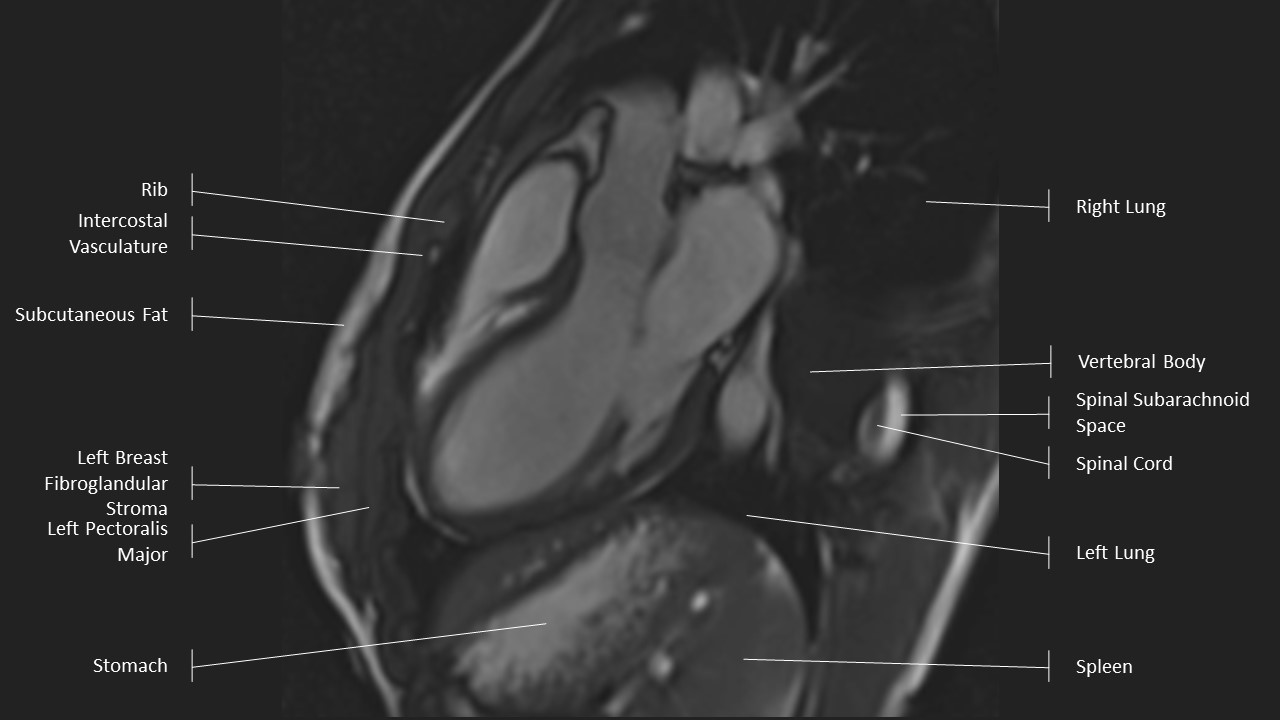

3 Chamber View